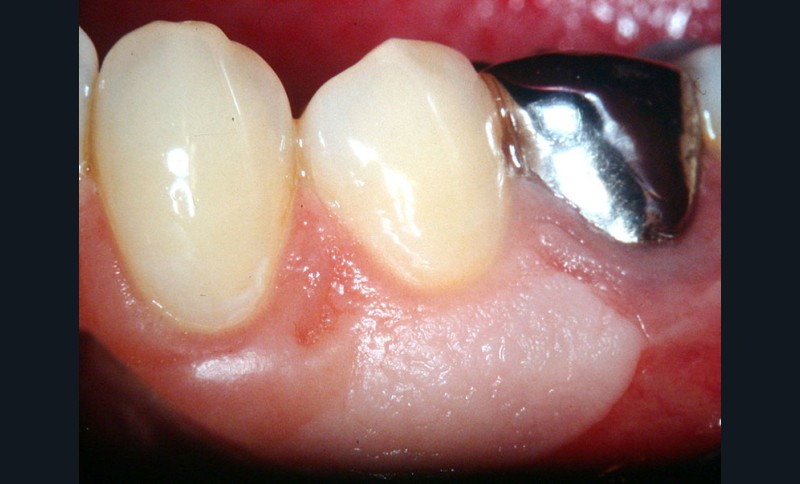

Cas clinique 1

Dans ce premier cas, la présence d’un complexe muco-gingival inadéquat (fig. 1) est observée sur une canine et une prémolaire.

Cette absence de gencive attachée peut prédisposer à la formation d’une récession gingivale. Une greffe épithélio-conjonctive est réalisée. Elle permet d’obtenir un lambeau de gencive attachée kératinisée stable (fig. 2).